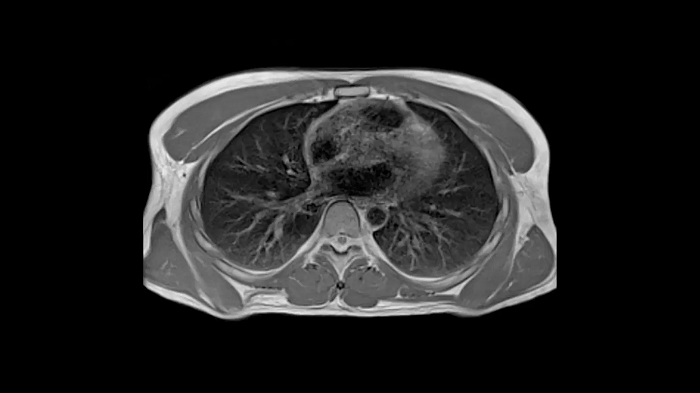

New opportunities in pulmonary imaging with High-V MRI

Pulmonary imaging has been disreputably challenging with traditional MRI as the air-tissue interfaces lead to fast signal decay. These challenges scale with magnetic field strength which makes High-V MRI the perfect opportunity for pulmonary imaging. Consequently, High-V MRI has the ability to extend the reach of pulmonary MRI.

Image Courtesy: University Hospital Erlangen, Germany | Image-ID: 4aaaa0419